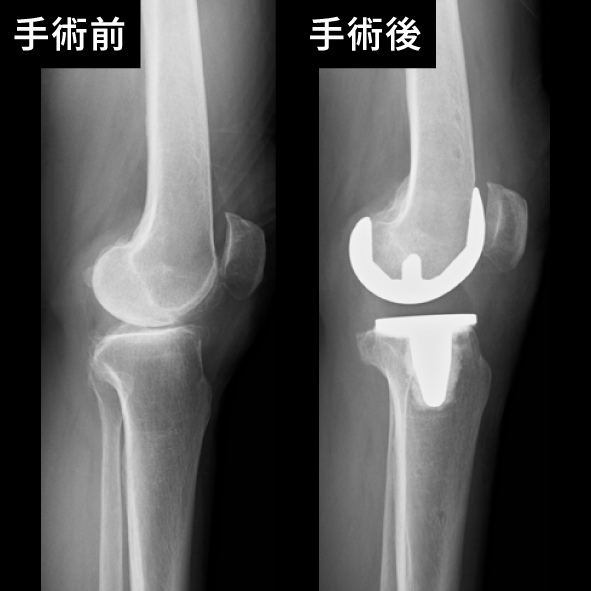

膝関節の手術前後

手術の種類には、関節全体を置き換える「全人工関節置換術」と、一部のみを置き換える「部分人工関節置換術」があり、患者さまの症状や状態に応じて選択されます。当院では、専門医が最新の技術を駆使して安全で精密な手術を行い、術後の回復を最大限にサポートします。

手術後は、リハビリテーションを通じて筋力や関節の可動域を回復し、日常生活や趣味、スポーツへの復帰を目指します。関節の痛みでお悩みの方は、人工関節手術をご検討ください。まずはお気軽にご相談ください。